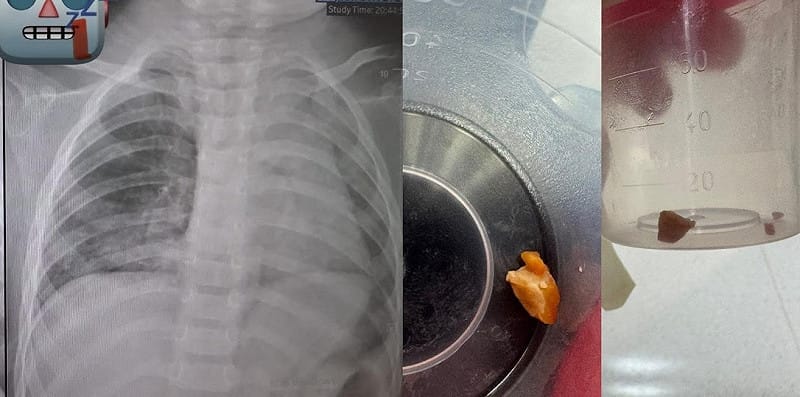

廖穗綾在臉書粉絲頁「廖穗綾醫師的健兒門診-Hablo Español」發布文章還原這起驚險案例。上週日病房收治一名1歲多孩子,家屬表示3、4天前阿嬤曾餵食花生,隨後孩子開始咳嗽並出現喘鳴聲。原本症狀並不明顯,未料隔天追蹤X光,發現孩子的肺部已經開始塌陷。廖穗綾表示,這絕對不是小事,當晚孩子隨即轉入加護病房,準備進行支氣管鏡異物取出作業。

手術過程極度艱難,廖穗綾指出,那顆花生已經卡在支氣管長達3天,周圍組織已增生肉芽,且整顆花生又大又肥,死死塞住氣管。賴醫師在手術後坦言,從未遇過這麼困難的案例,整整將近2個小時,醫療團隊在狹小的氣道裡反覆嘗試,就在幾乎要放棄的時刻,那顆「會跳舞的花生」終於彈動了一下,才成功被網住夾出,在場醫護人員這才鬆了一口氣。